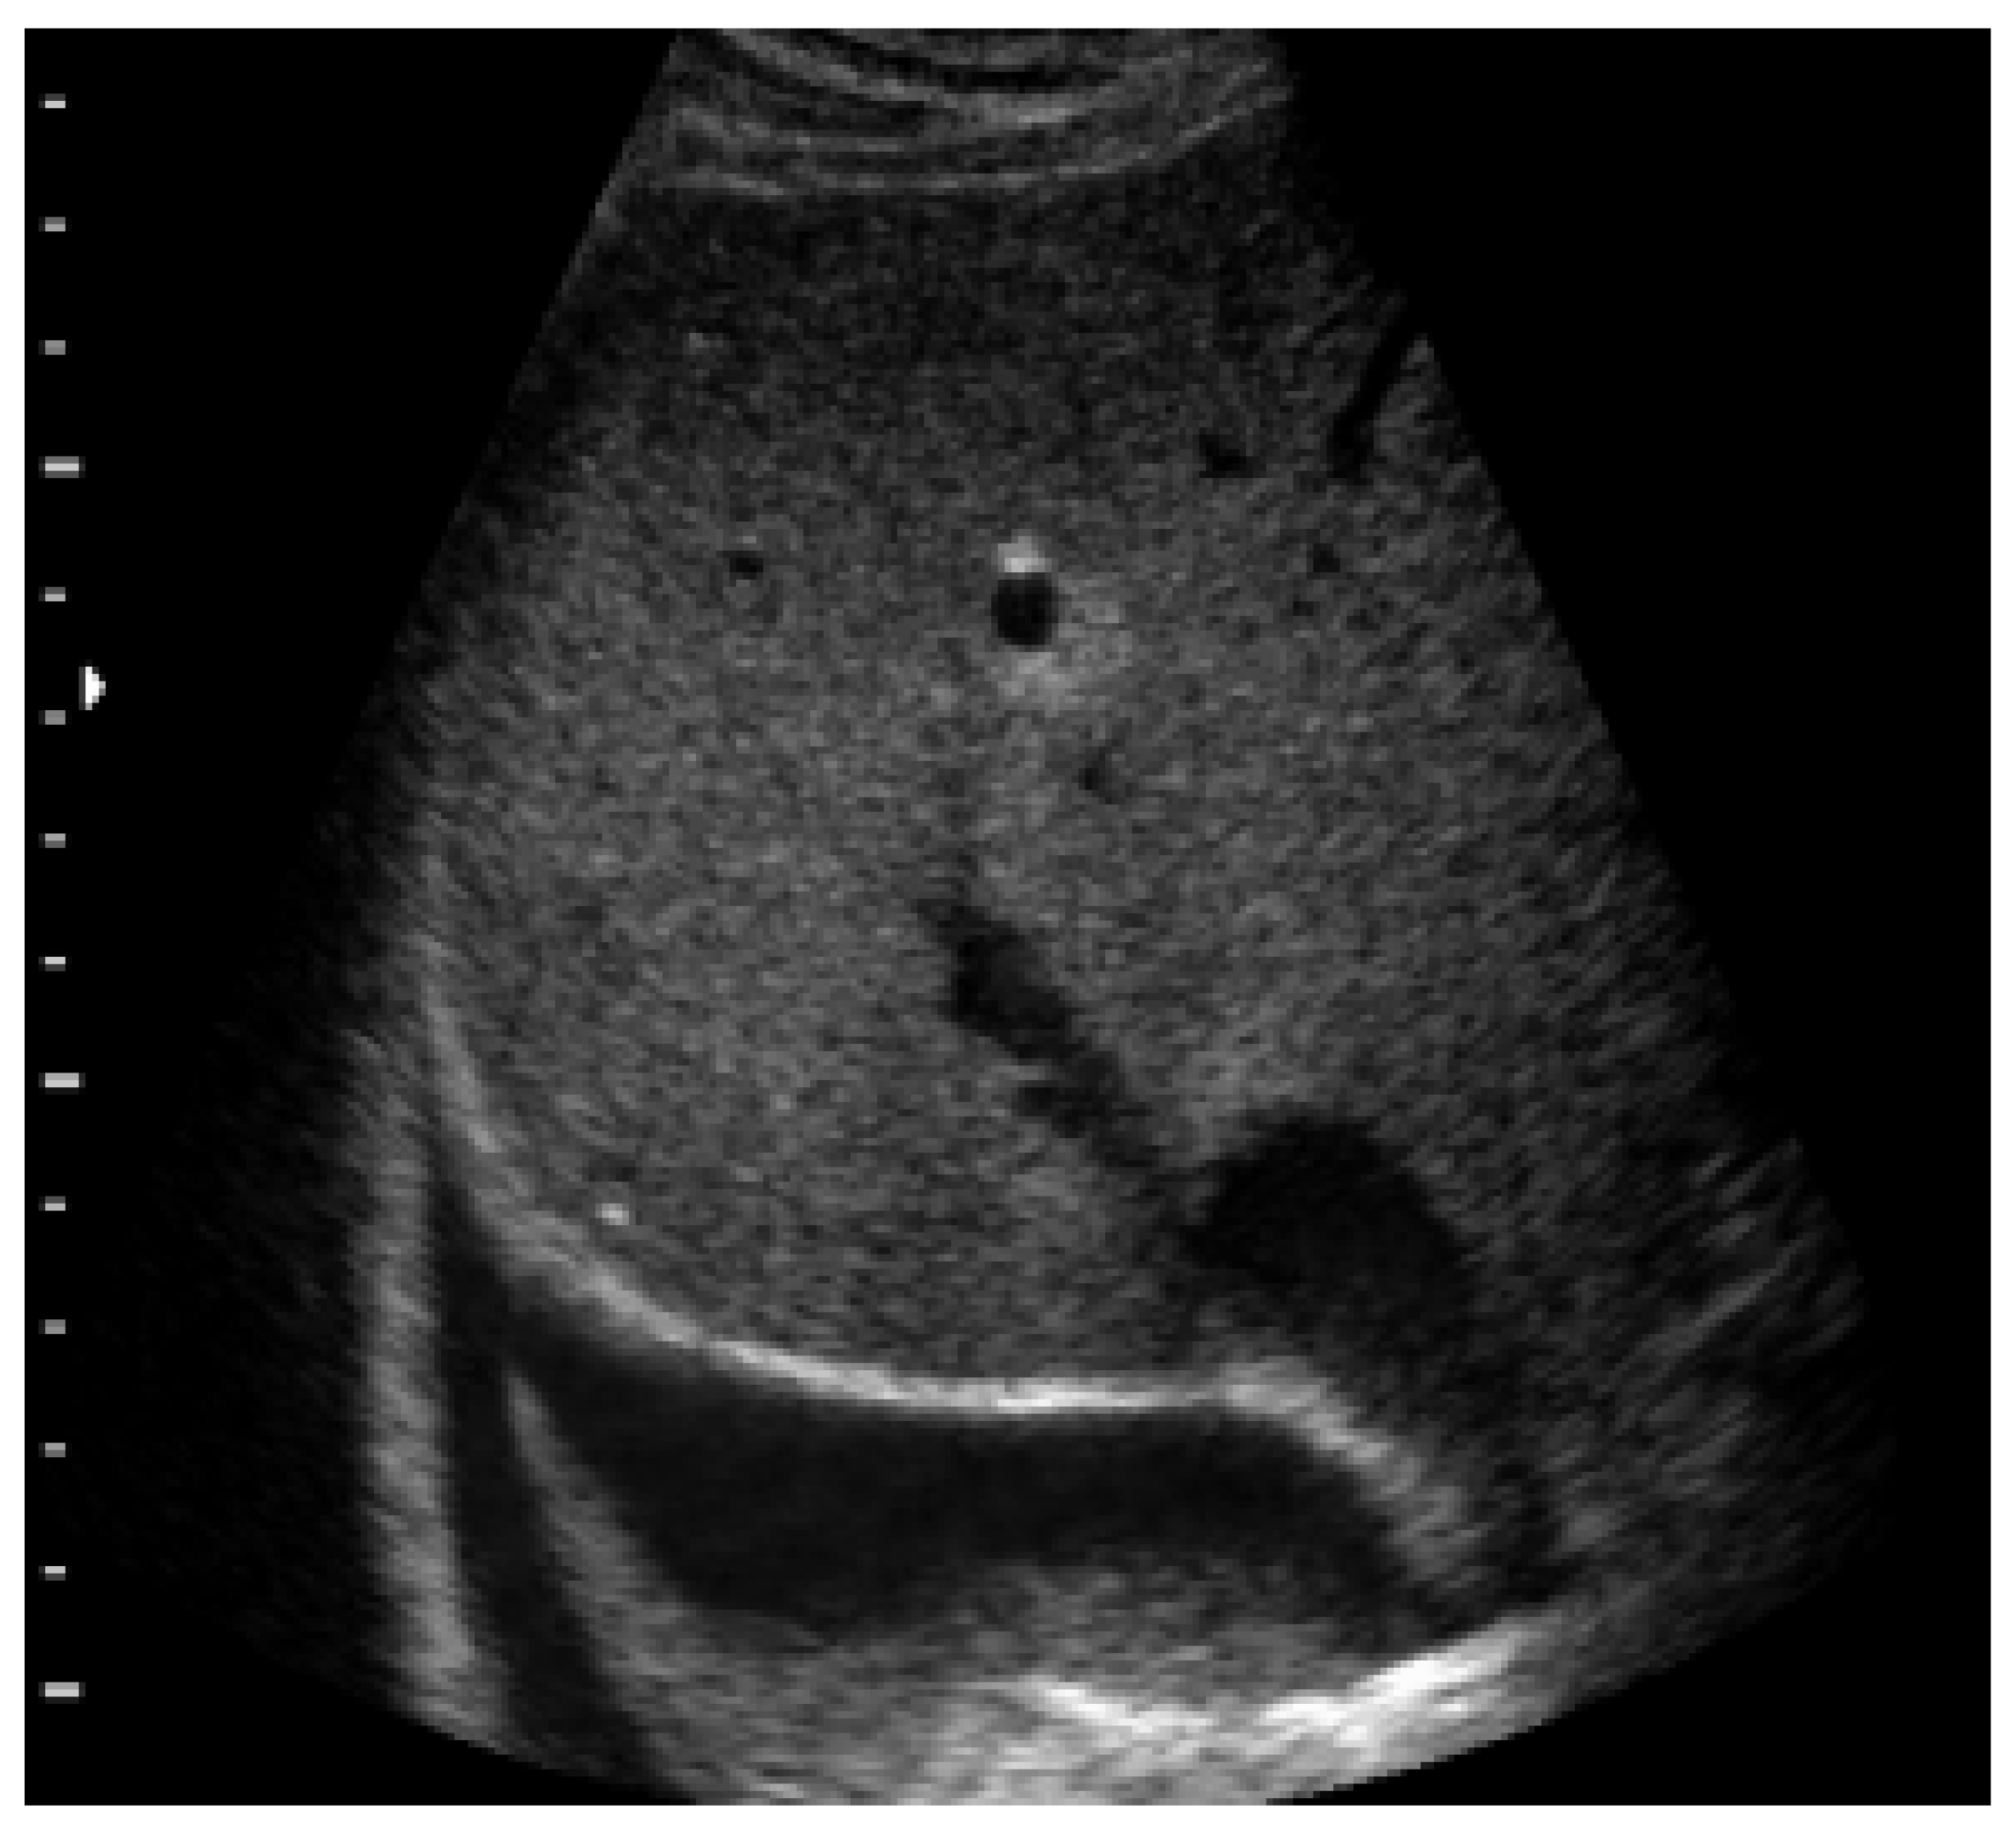

4.5. Pulmonary Edema